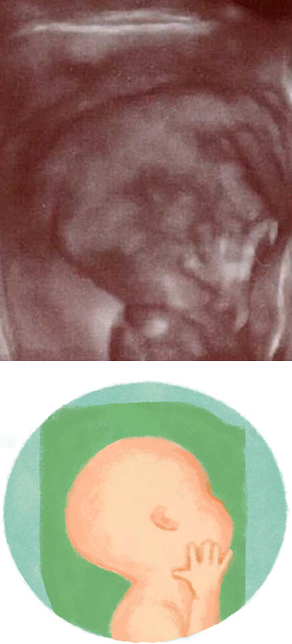

妊娠17週ころの超音波写真

おなかの赤ちゃんの成長【16~19週ごろ】

●骨が丈夫になり、筋肉がついてきます。

●皮下脂肪がつき始めます。

●体の動きが豊かになり、上体を後ろに反らす、足を前にグーンと伸ばす、首を左右に振る、手の指を握るなどの動きをするようになります。

●皮膚に厚みが出て赤みがかり、全身に産毛が生えます。

●髪の毛が生えます。

●手を口元にもってくるなどのしぐさをすることも。

赤ちゃんの骨はやわらかい軟骨ですが、さらに丈夫になり、筋肉がついてきます。皮下脂肪がつき始めるのもこのころ。そのため、体の動きが少しずつ大きくなってきます。胎動をママが感じ取れるまで、あとちょっと!